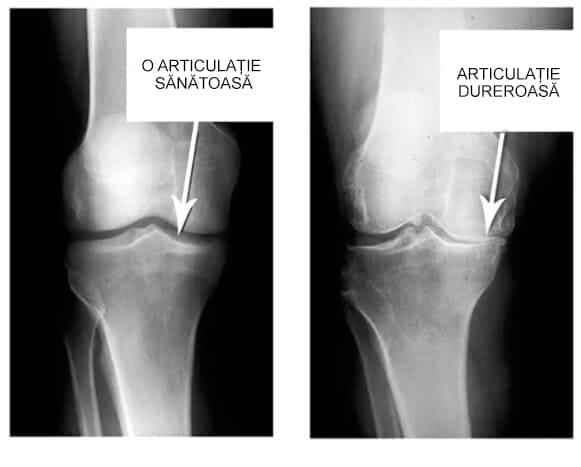

Uitați-vă la aceste imagini, puteți vedea că în imaginea din dreapta nu există un spațiu articular, oasele se freacă una de alta, provocând multă durere. Iar acest proces este foarte greu de oprit !

Cât timp credeți că este nevoie pentru ca țesuturile să se degradeze și articulația să se uzeze?".